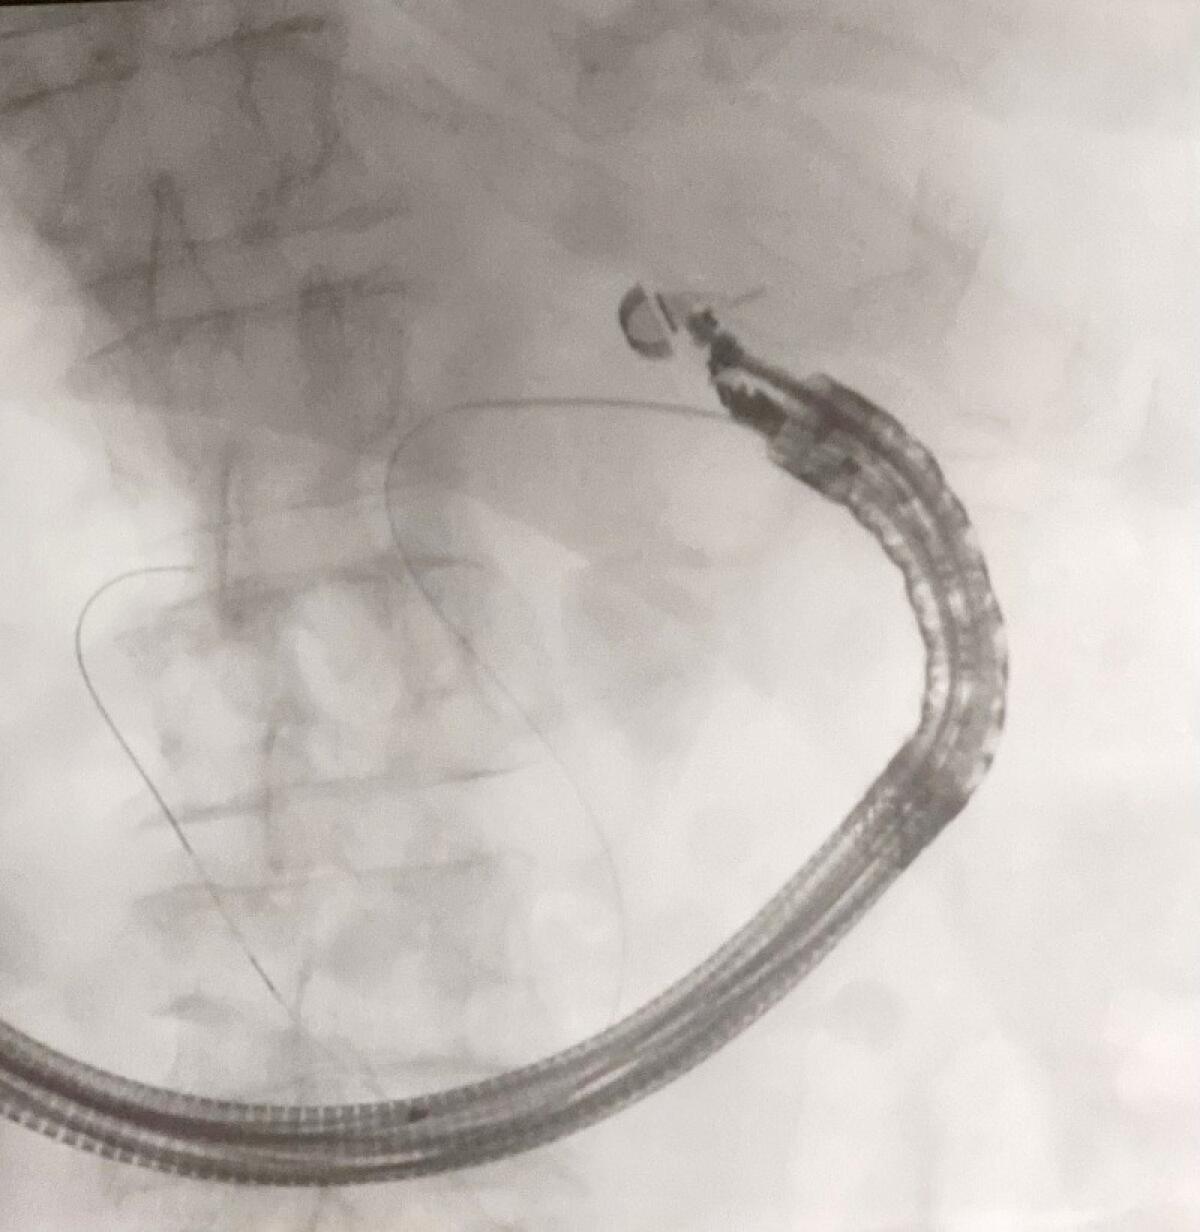

Tecnica di “rendez-vous” per la rimozione “difficile” di un calcolo

La donna era stata ricoverata per una colangite acuta causata da un calcolo nel coledoco, il principale condotto biliare. La situazione si è complicata durante il tentativo di rimuovere il calcolo tramite colangio-pancreatografia endoscopica retrograda (ERCP), poiché la via biliare principale si è rivelata inaccessibile. I ripetuti tentativi non hanno avuto successo a causa della conformazione della papilla, che risultava fibrotica e dura.

A questo punto, gli specialisti del team guidato dal dottor Santo Grasso hanno adottato una strategia innovativa: un intervento endoscopico combinato noto come “Rendez Vous”. Questa tecnica prevede l’utilizzo dell’ecoendoscopia per fissare l’accesso al condotto biliare e un’ERCP convenzionale per completare l’intervento.